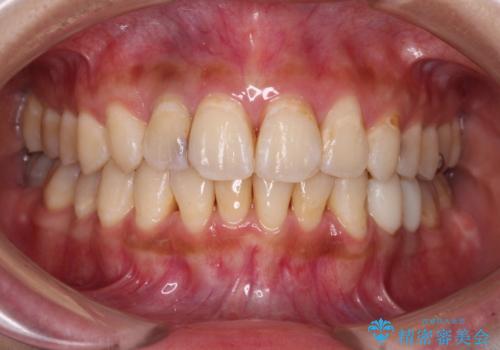

以前治療した前歯をきれいに治したい オールセラミッククラウン

- 根管治療はやり直さずに、ファイバーポストを使用した土台を植立して、オールセラミッククラウンにて補綴することとしました。

神経を取り除いた歯の変色は、クリーニングやホワイトニングでは改善できないため、オールセラミッククラウンなどによる補綴治療が必要となります。